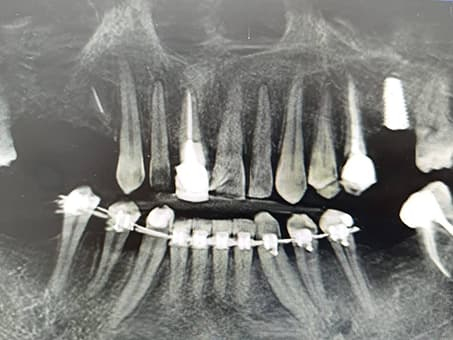

1. Диагностика

Тщательный осмотр и 3D моделирование строения нужного участка ротовой полости. Данная процедура проходит при помощи лучшего в Казахстане томографа немецкой фирмы Sirona.

Компьютерная диагностика на начальном этапе лечения позволяет врачу детально представить состояние и количество костной ткани, особенности строения ротовой полости пациента, а также вовремя выявить скрытые заболевания — кисты, гранулемы и пр.

Трехмерное моделирование позволяет правильно рассчитать расположение будущих имплантатов и буквально до микрона определить угол вхождения штифтов в челюсть.

4. Имплантация

Это основной этап. Основной этап также делится на 2 этапа — хирургический и ортопедический. На первом этапе имплантации зубов происходит установка выбранных имплантатов в костную ткань и контроль над процессом выздоровления. На втором (ортопедическом) этапе, изготавливается коронка и устанавливается на хорошо прижившийся стержень. Рассмотрим процесс имплантации зубов детальнее:

Хирургический этап: установка импланта

На этом этапе имплантации зубов титановый имплант вживляется в костную ткань под местной анестезией. Процедура занимает в среднем 30–60 минут и проходит безболезненно. После установки начинается процесс остеоинтеграции — срастания импланта с костью, который длится в среднем от 2 до 3 месяцев.

Наши работы